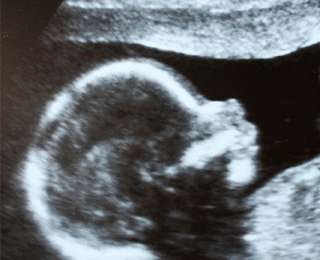

92-лентняя чилийка обратилась к медикам из-за сильных болей в руке, начавшихся после неудачного падения. Проведя полное обследование престарелой пациентки, специалисты сделали весьма неожиданное открытие — в утробе пенсионерки находился плод весом в два килограмма, срок вынашивания которого составлял около 30 недель. При этом зачат ребенок был не менее 50 лет назад.

Как сообщает местное издание La Tercera, женщина не знала о своем «интересном» положении. Доктора объяснили, что у нее была внематочная беременность, а эмбрион закрепился к брюшной полости. В результате этого вместо симптомов беременности женщина чувствовала опухоль внизу живота. На 30 неделе развития плод погиб и мумифицировался, и все эти годы не доставлял «матери» никаких неудобств.